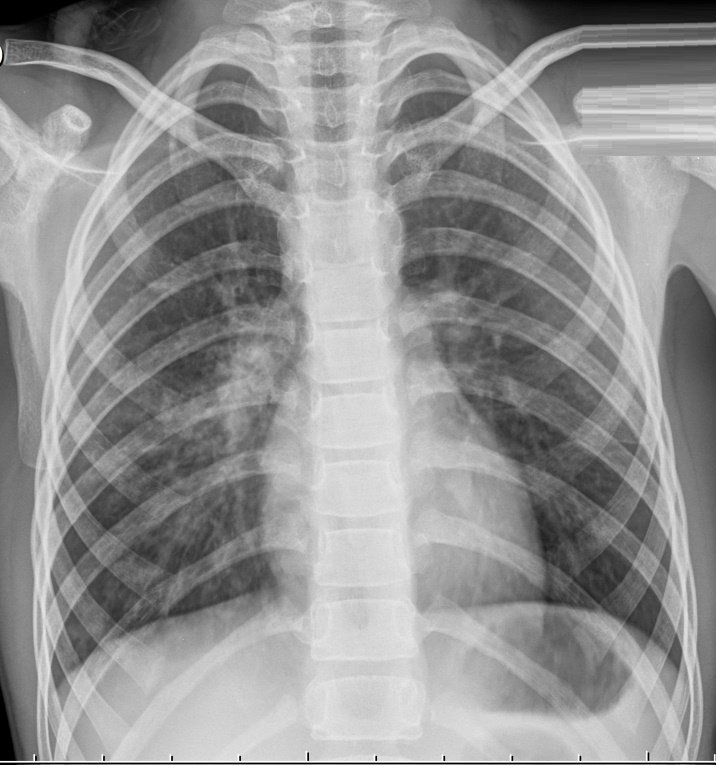

Рентген снимок атипичной пневмонии

Атипичная пневмония — собирательный термин, включающий инфекционно-воспалительные поражения тканей лёгких. Причинами являются нехарактерные возбудители — микоплазма, хламидия, легионелла, вирусы. Воспаление лёгких протекает с повышением температуры, одышкой, общим недомоганием.

Диагностировать патологический процесс можно при помощи рентгена. Так, для микоплазменной формы характерна неоднородная инфильтрация лёгочной ткани, она может определяться слабо или быть среднеинтенсивной.

При легионеллезной, на снимке видно уплотнения (инфильтраты) округлой формы, локализующиеся на поверхности одной доли лёгкого. В ряде случаев наблюдается слияние инфильтратов.

У 25% пациентов одновременно с пневмонией определяется плеврит, с незначительным скоплением секрета в плевральной полости.

Практически невозможно отличить пневмонию Legionella от других, основываясь на таком методе обследования. Присутствие легионеллы или хламидии подтверждается серологическим анализом крови.

При атипичной пневмонии легких на рентгеновском снимке видны затемнения:

- мелкоочаговые – не более 3 мм;

- среднеочаговые – не более 7 мм;

- крупноочаговые – не более 12 мм;

- фокусные – более 12 мм.

Атипичная пневмония на рентгеновском снимке: